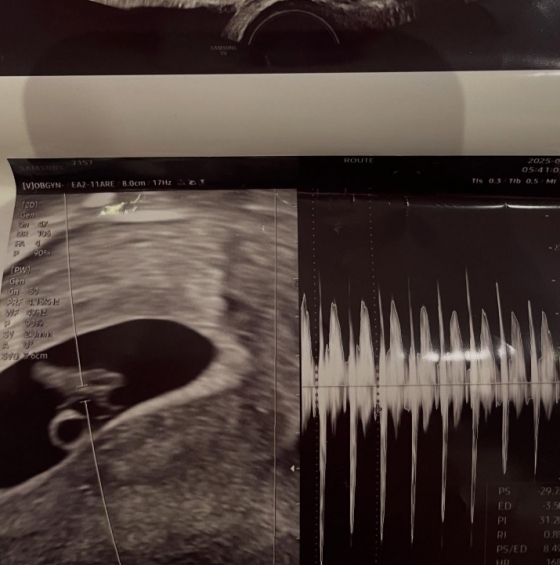

그러면서 서민재는 A씨의 인스타그램 계정과 그가 다니는 듯한 회사와 학교 등을 태그하며 연락을 압박하는 것으로 보인다. 앞서 서민재는 초음파 사진과 함께 임신 사실을 공개했고, 남자친구의 실명을 공개하며 "20학번이고, 97년생"이라고 밝힌 바 있다.

그러면서 서민재는 A씨의 인스타그램 계정과 그가 다니는 듯한 회사와 학교 등을 태그하며 연락을 압박하는 것으로 보인다. 앞서 서민재는 초음파 사진과 함께 임신 사실을 공개했고, 남자친구의 실명을 공개하며 "20학번이고, 97년생"이라고 밝힌 바 있다.